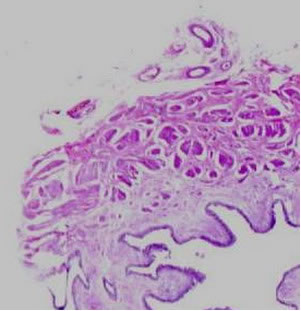

Третий тип: соединительная ткань занимает более 75% длины

периметра мочеточника.

В докладе также приведены основные мофологические изменения

в зависимости от типа распределения соединительной ткани

в стенке мочеточника с использованием микроскопии и гисто-химических

исследований.

Автором сделаны выводы о снижении эффективности оперативного

лечения при наличии воспалительной реакции и наличии атрофичных

клеточных форм в стенке мочеточника при обструктивных формах

мегауретера.